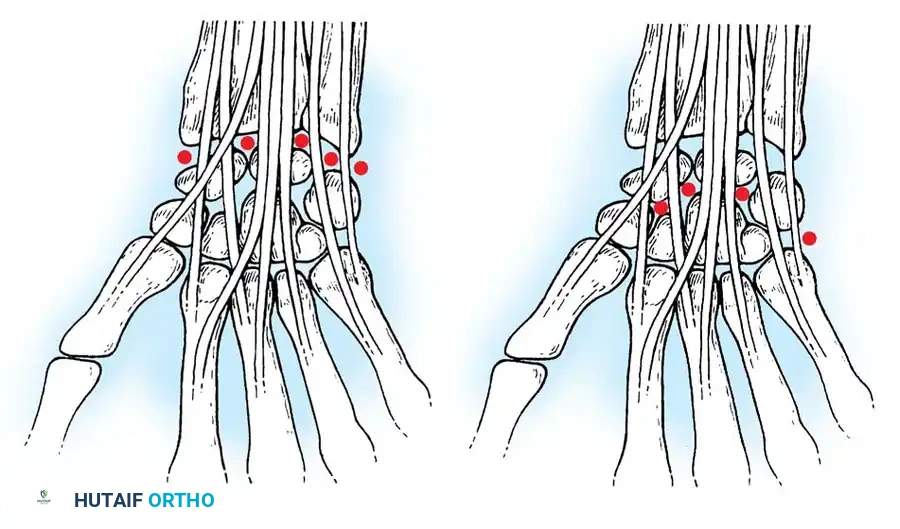

Wrist arthroscopy portals are anatomically defined by their relationship to the six dorsal extensor compartments. Precise portal placement is critical to avoid injury to cutaneous nerves, extensor tendons, and articular cartilage.

Radiocarpal Portals

- 1-2 Portal: Located between the first compartment (APL, EPB) and the second compartment (ECRL, ECRB). It is situated in the anatomic snuffbox. Risk: The superficial branch of the radial nerve (SBRN) and the radial artery.

- 3-4 Portal: The primary viewing portal. Located between the third compartment (EPL) and the fourth compartment (EDC), just distal to Lister's tubercle. It provides an excellent panoramic view of the SL ligament, volar ligaments, and the radial aspect of the TFCC.

- 4-5 Portal: The primary working portal. Located between the fourth compartment (EDC) and the fifth compartment (EDM). It provides direct access to the TFCC and the LT ligament.

- 6R Portal: Located immediately radial to the sixth compartment (ECU tendon). Used for viewing the ulnar periphery of the TFCC and the ulnocarpal ligaments.

- 6U Portal: Located immediately ulnar to the ECU tendon. Risk: The dorsal sensory branch of the ulnar nerve (DSBUN).

Midcarpal Portals

* Midcarpal Radial (MCR) Portal: Located approximately 1 cm distal to the 3-4 portal, in a palpable soft depression between the capitate, scaphoid, and lunate. It is in line with the radial border of the third metacarpal.

* Midcarpal Ulnar (MCU) Portal: Located approximately 1 cm distal to the 4-5 portal, aligned with the axis of the fourth metacarpal, providing access to the triquetrohamate and lunotriquetral articulations.